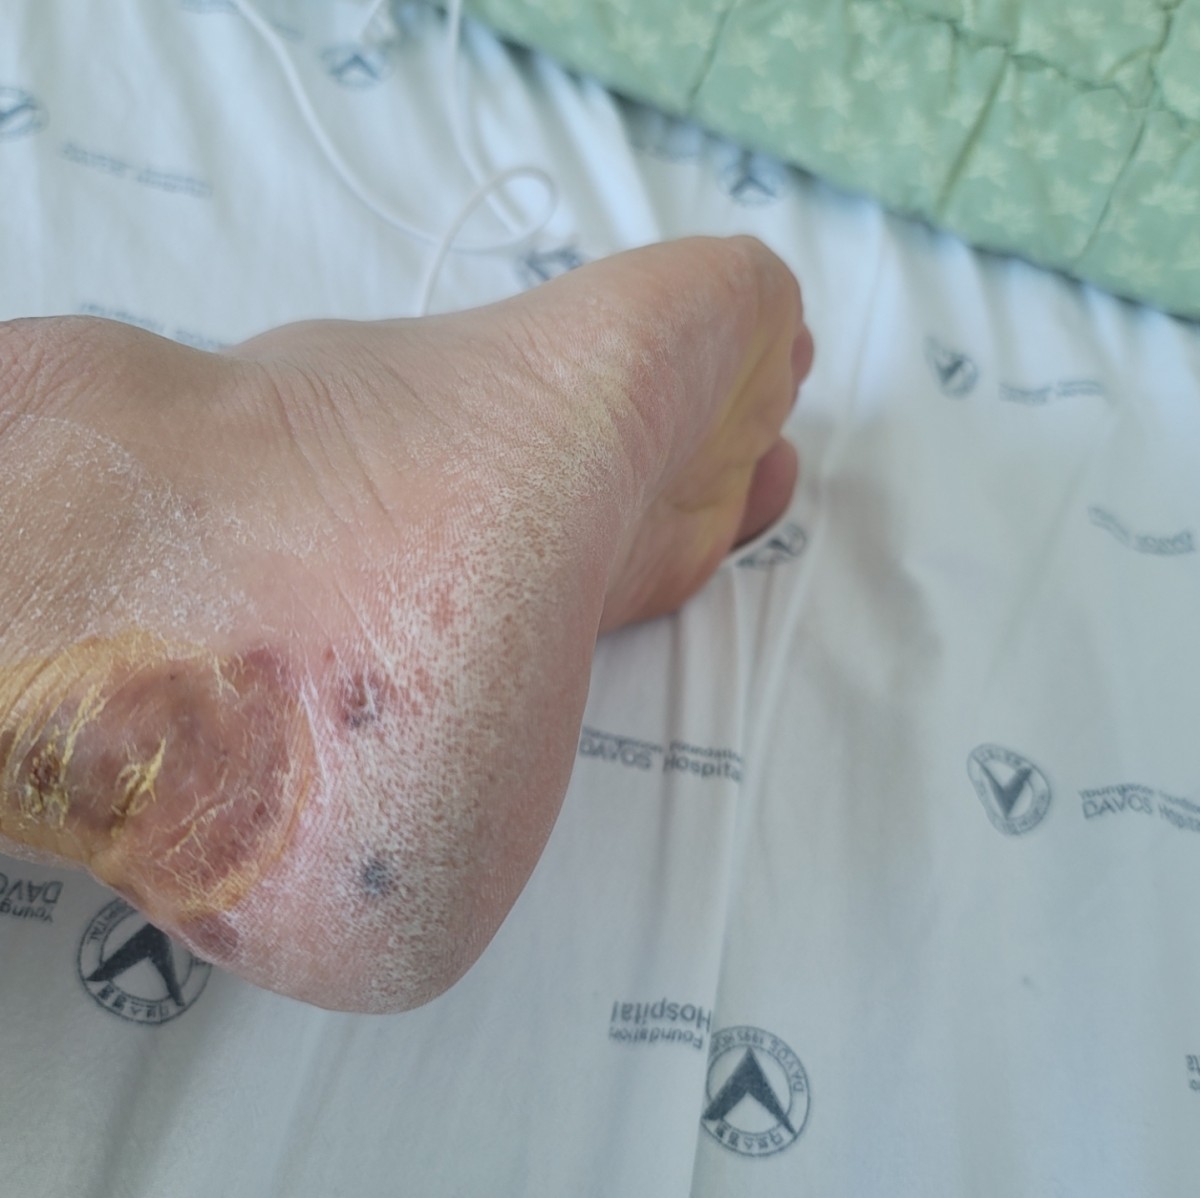

3년전부터 겨울 12월경이 되면 잠들기전에 오른쪽 뒷꿈치부위가 가려워서 긁고나면 아침에 빨갛게 부어 있습니다. 그리고 나서 가려운 증상은 없어지고 빨간 반점들이 한두개 생기면서 염증이 발생됩니다. 그리고 일주일이 지나면 부위가 넓어지면서 살짝만 닿아도 엄청난 고통이 생깁니다. 작년에는 종합병원에 입원했는데 치료가 잘 되지 않아서 한달 넘게 입원을 했습니다.

MRI,CT,X레이 찍었고 결과는 그냥 염증으로 나왔습니다.

그리고 여러군데 피부과와 정형외과도 가보았고 통풍이 있어 통풍인지 알고 엄청 잘한다는 뉴마티스내과도 방문하여 진료늘 받았는데 원인을 찾지 못했습니다.

작년때 증상 사진하고 지금 사진 보내드립니다. 같은 증상으로 치료 하신적이 있는지 살펴봐 주시면 감사하겠습니다.